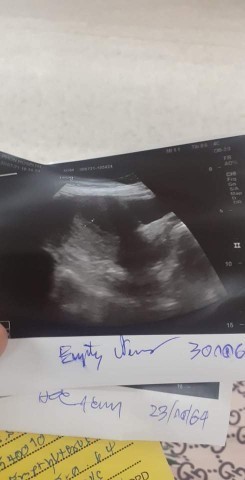

#ท้องแรกคะ คือหนูซาวน้องเมื่อ2อาทิตย์ที่เเล้วเเล้วเจอถุงตั้งครรภ์น้องได้5w6dเเล้ววันอังคาร 7wไปซาวทางช่องคลอดเเต่ยังไม่เจอตัวน้องเเม่ๆคนไหนซาวทางช่องคลอดรึหน้าท้องเจอน้องช้าไหมคะเจอตอนกี่วีคตอนนี้กังวลมากเลยค่ะ#ขอบคุณสำหรับคำตอบค่ะ

เพื่อนดิฉันมีถุงตั้งครรภ์แต่ไม่มีตัวอ่อนตอน 6 w คุณหมอให้หยุดการตั้งครรภ์เลยค่ะ เพราะถุงตั้งครรภ์โตขึ้น แต่ไม่พบตัวอ่อนค่ะ...คุณแม่ลองไปตรวจดูนะคะ และปรึกษาคุณหมอให้แน่ใจ เป็นกำลังใจให้คะ

บ้านนี้5วีค6วันเจอถุงการตั้งครรภ์และเจอตัวน้องคือเล็กมากๆแต่ยังไม่เจอคลื่นหัวใจของน้องเลยค่ะ อาทิตย์หน้าหมอนัดอีกทีถ้าน้องไม่โตขึ้นก็คงจะได้เอาน้องออก

แม่บ้านนี้หยังไม่เจอคลื่นหัวใจน้องเลยค่ะ หมอนัดพรุ่งนี้ถ้าซาวแล้วน้องยังไม่โตขึ้นหรือยังไม่เจอคลื่นหัวใจหมอจะไห้ขูดมดลูกเลยค่ะ

ของเรา5วิคแต่มีเลือดแค่หยดสองหยดตลอดสามวันไปซาวอีกรอบ ไม่เจอเหมือนกันคะพอดีมีโรคประจำตัวความดันสูงอาทิตหน้าถ้าไม่เจอหมอยุติการตั้งครรให้คะ

ตอน4วิคเจอถุงการตั้งครรคะแล้วหมอบอกว่าเล็กลงเหมือนไม่เจริญเติปโตแล้วจะหลุดออกมาเองคะ

ซาวด์ครั้งเเรกผ่านช่องคลอดตอน4wเจอเเต่ถุงการตั้งครรภ์ค่ะ อีกครั้งซาวด์หน้าท้องตอน7w เจอน้องแล้วได้ยินเสียงหัวใจน้องค่ะ🥰

แม่บ้านนี้ซาวด์หน้าท้องไม่เจอน้องคะ หมอเลยซาวด์ผ่านช่องคลอด เจอน้องคะ6 W4D พร้อมเสียงหัวใจคะ

ของบ้านนี้เจอตอน 8 W6D คะ อย่าเพิ่งเครียดคะ ตอน 7 w ไปซาวก้อไม่เจอเหมือนกันคะ

บ้านนี้ซาวทางช่องคลอด6วีค เจอหัวใจเต้นแล้วคะ อาจจะยังเล็กอยู่แม่ใจเย็นๆนะคะ